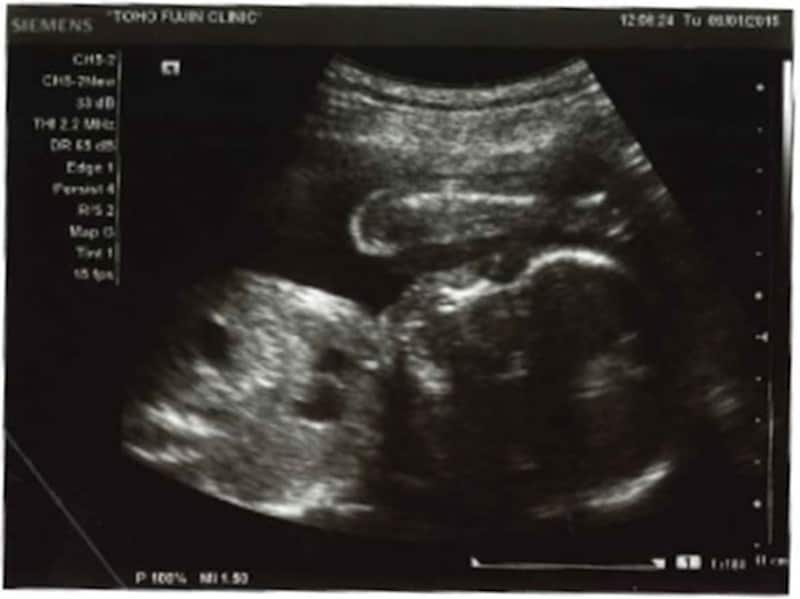

妊娠9ヶ月の胎児の発達や母体の症状

妊娠9ヶ月の胎児は、いまや4頭身に成長しています。元気で産まれてきてくれれば、早産ではありますが、子宮外での生活が可能になっています。

妊娠9ヶ月目 妊娠32~35週の胎児の様子・母体の症状や気を付けること